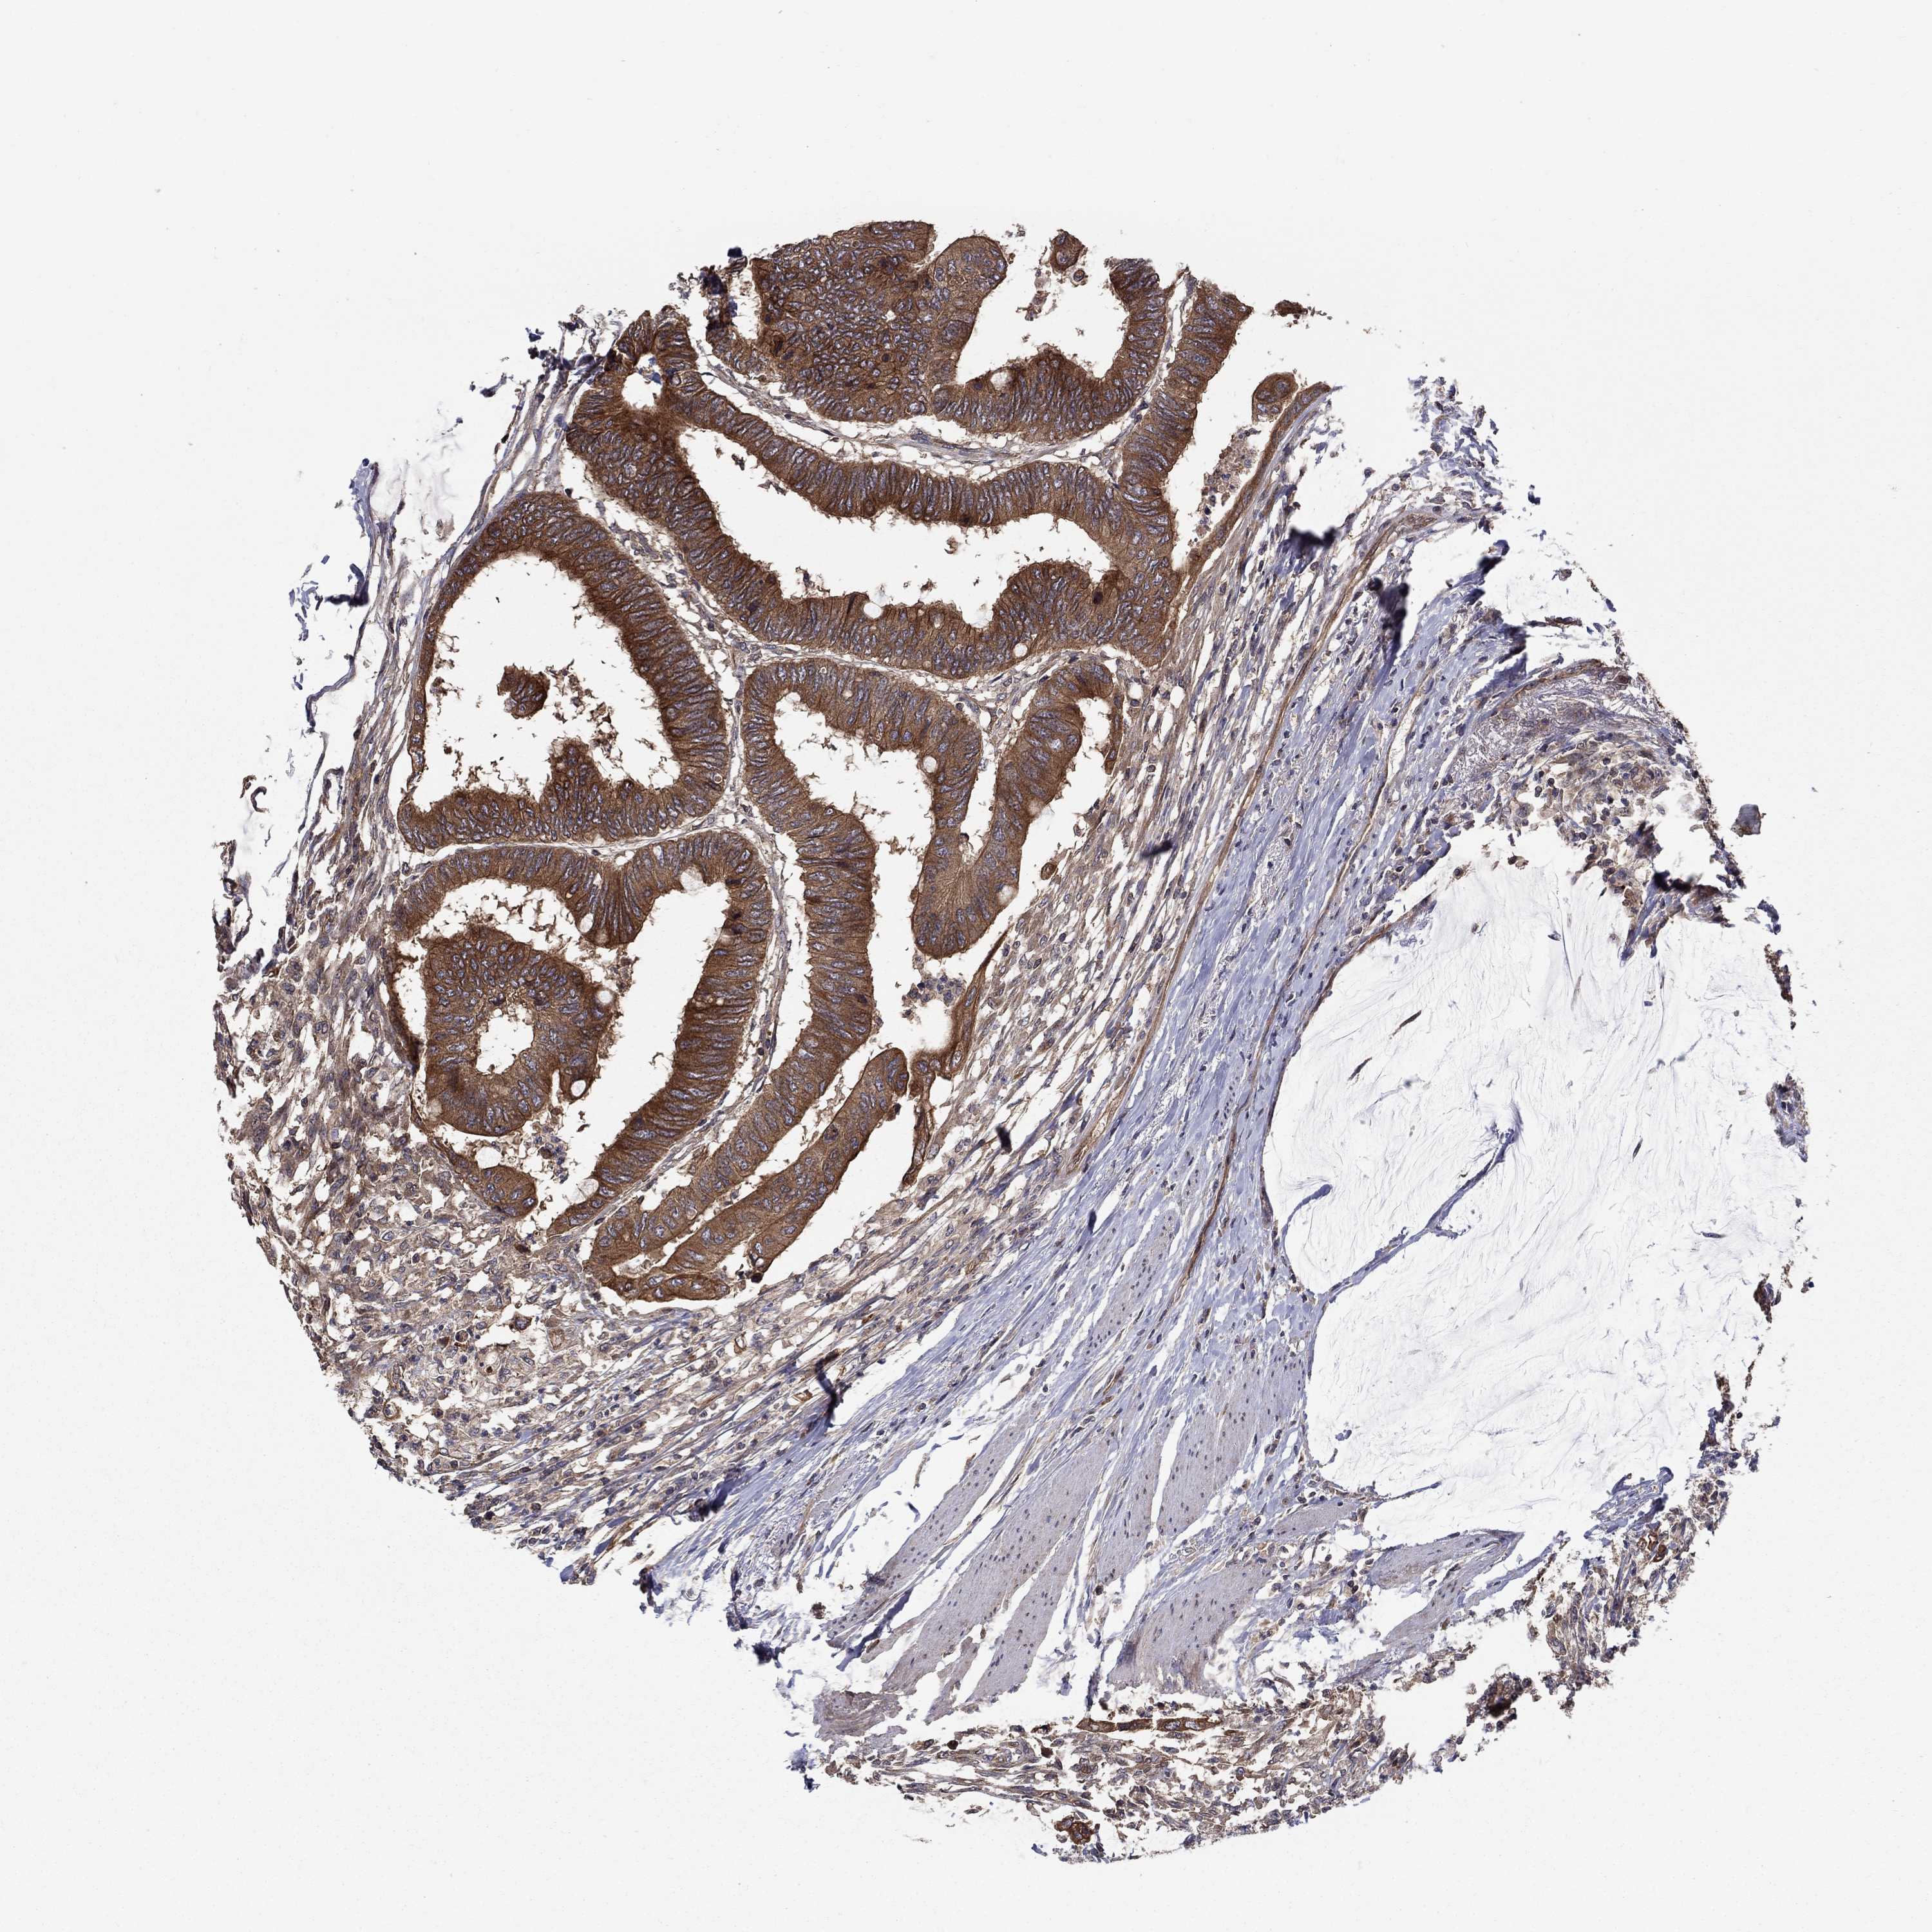

CANCER COLORECTAL CANCER Show tissue menu

Colorectal cancer

Human cancer

Colon adenocarcinoma